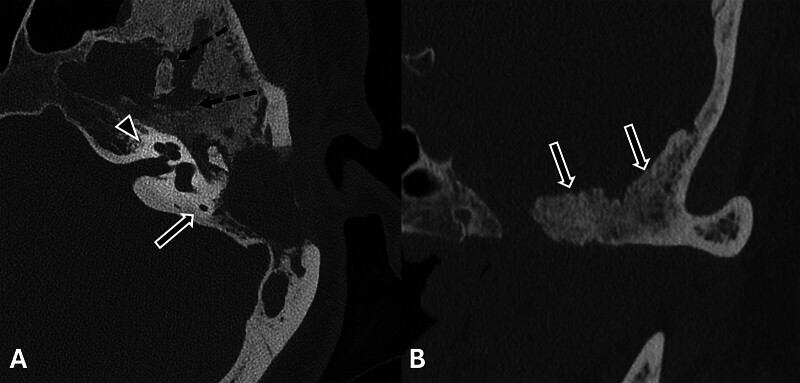

Temporal bone en plaque meningiomas can present management challenges, particularly when accompanied by severe pain. We report the case of a 42-year-old woman who was initially diagnosed with chronic otitis media but was later found to have a painful left temporal bone en plaque meningioma. Despite conservative therapy, her pain progressed, prompting the decision to undergo surgical resection, which resulted in considerable pain relief. This report illustrates the influence of pain on surgical decision-making for temporal bone en plaque meningiomas and reviews the literature on their variable presentations and management strategies.